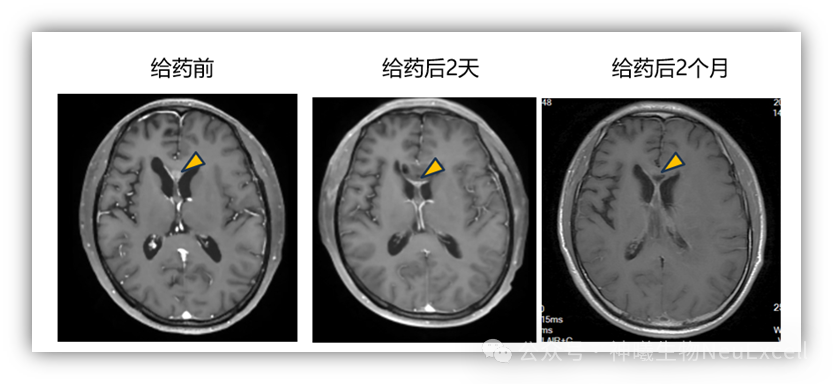

研究共纳入11例手术及放化疗后复发的恶性脑胶质瘤患者,受试者入组后接受手术切除肿瘤+NXL-004瘤腔内注射(n=10),或接受病理活检后+NXL-004瘤内注射(n=1)。主要研究结果如下:安全性:NXL-004具有良好的安全性,未观察到药物相关严重不良事件或剂量限制性毒性;有效性:接受NXL-004治疗后,全部受试者预期中位总生存期(OS)超过12 个月,显著优于历史数据(6-9个月)。至发稿为止,首例患者生存期超过 18 个月。在瘤内注射患者中,观察到明确的治疗反应,靶病灶显著缩小超过 90%(图1)。